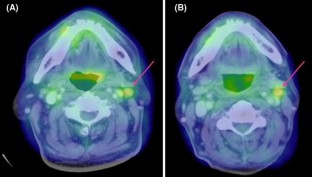

Fig. 3